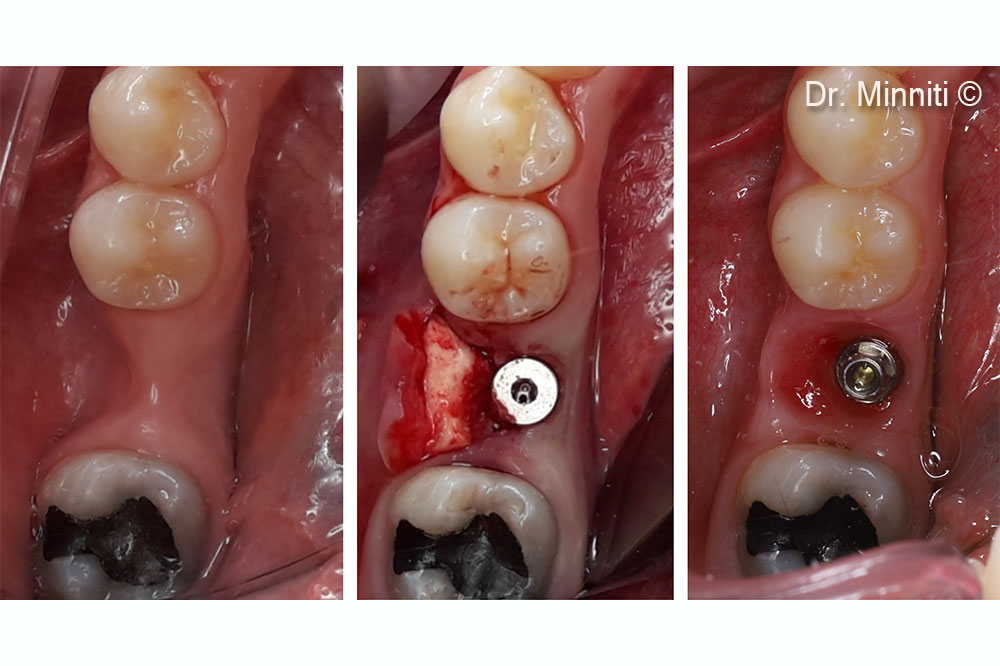

Tình hình ban đầu

Một bệnh nhân nữ (37 tuổi) có biểu hiện teo mô mềm nghiêm trọng theo chiều ngang và chiều dọc.

Vật liệu sinh học đã qua sử dụng

Derma

Một bệnh nhân nữ (37 tuổi) có biểu hiện teo mô mềm nghiêm trọng theo chiều ngang và chiều dọc.

Derma